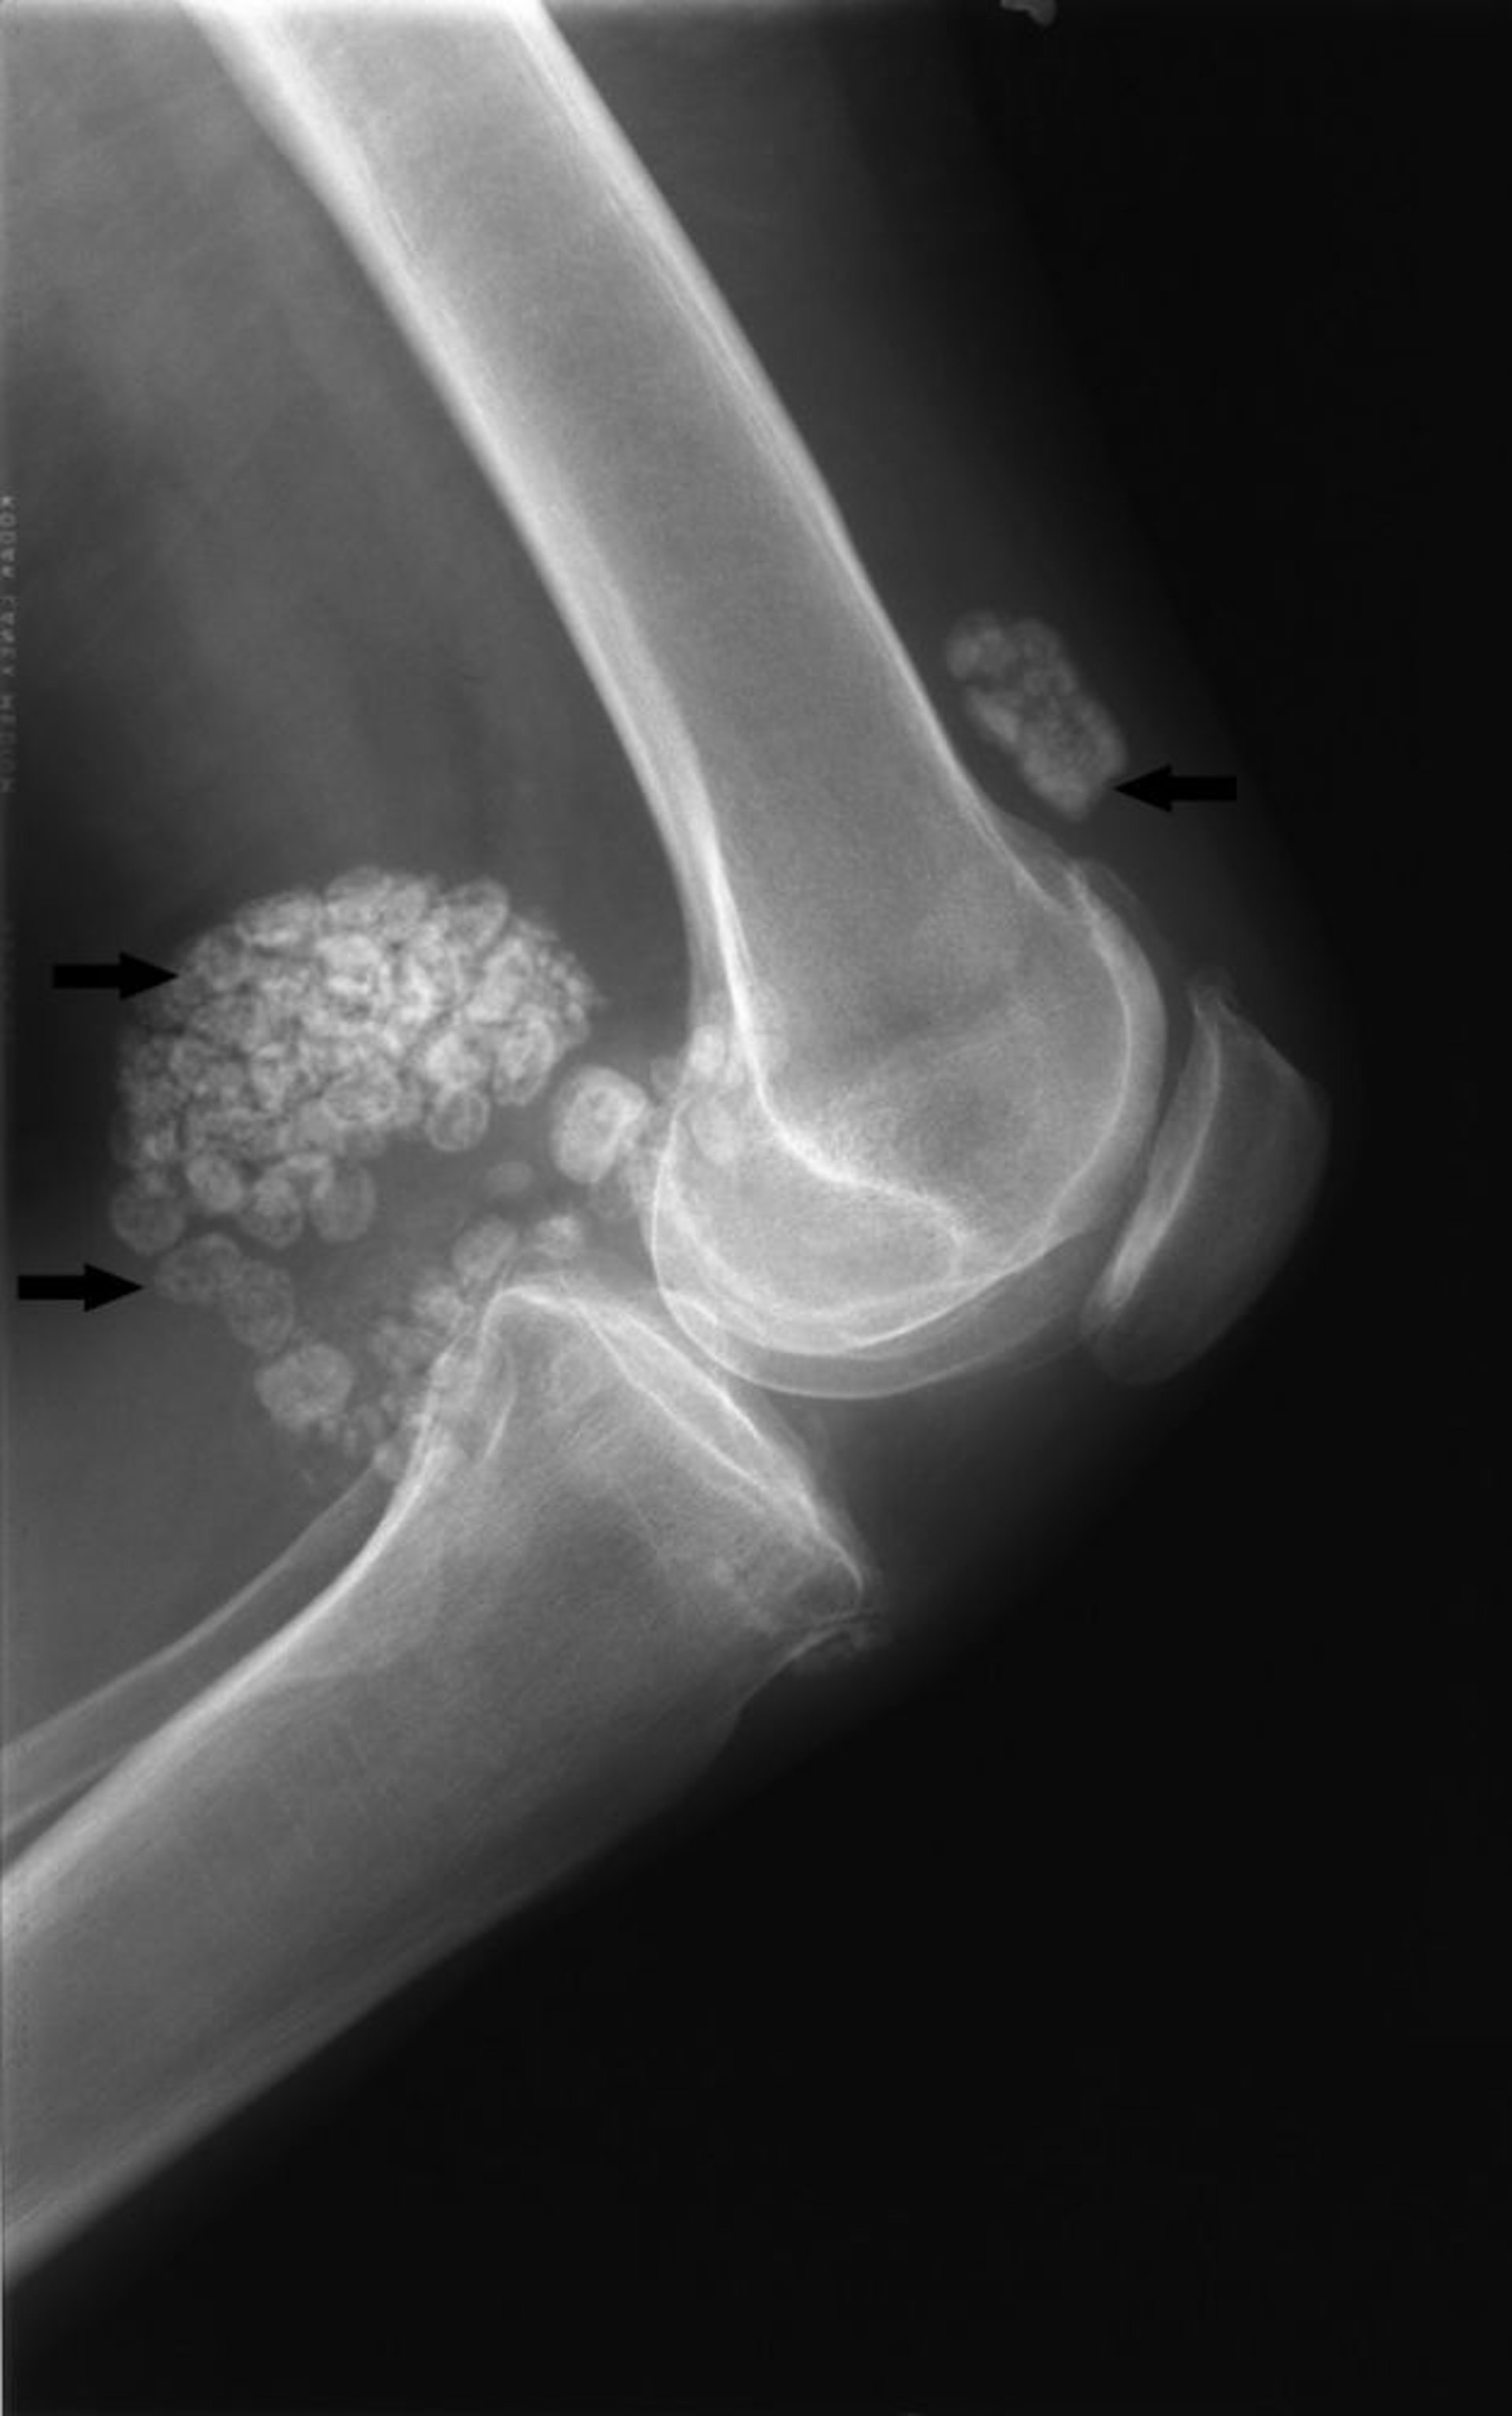

Condromatosis sinovial

Esta radiografía de la rodilla muestra múltiples cuerpos calcificados articulares grandes tanto delante como detrás de la articulación (flechas), y es típica de la condromatosis sinovial.

Image courtesy of Michael J. Joyce, MD, and Hakan Ilaslan, MD.